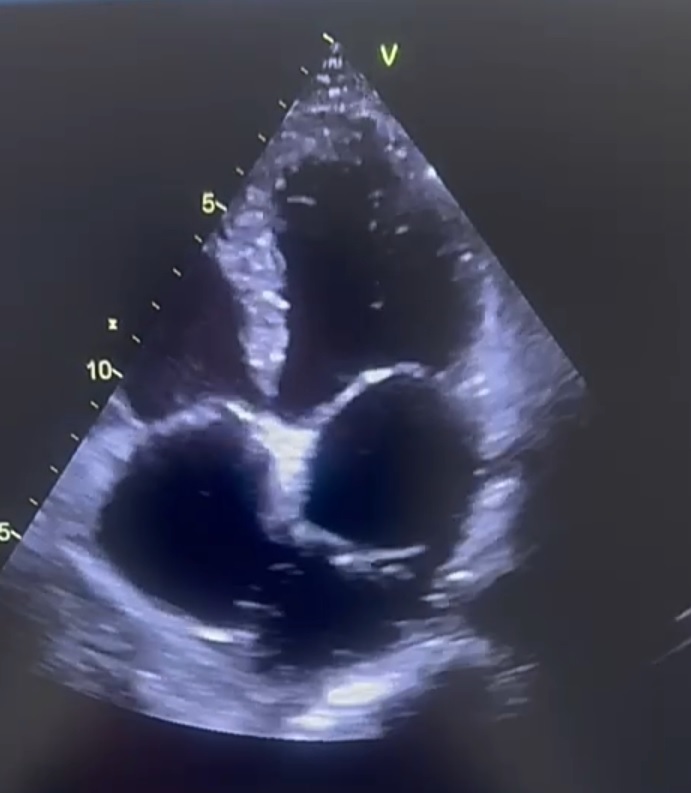

Un homme de 45 ans, sans antécédent de cardiopathie ni de facteur de risque cardiovasculaire, consulte pour une dyspnée d’effort de stade 2 de la New York Heart Association (NYHA) et des palpitations intermittentes. L’examen clinique révèle un souffle systolique d’intensité modérée au foyer tricuspidien sans signes d’insuffisance cardiaque droite. L’échocardiographie transthoracique et transœsophagienne montre une membrane totale dédoublant l’oreillette gauche en deux compartiments avec un shunt gauche-droite et une hypertension pulmonaire importante. Une exérèse chirurgicale de la membrane est décidée ; les suites ont été simples.

Le cœur triatrial est une malformation rare résultant de la persistance anormale d’une structure embryonnaire séparant l’oreillette gauche ou droite en deux compartiments. La détection à l’âge adulte est exceptionnelle et repose essentiellement sur l’échocardiographie transthoracique, qui permet de visualiser la membrane séparatrice.